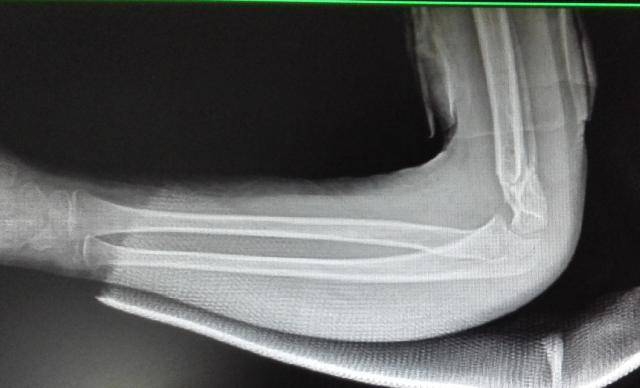

典型病例:中醫(yī)手法整復(fù),夾板固定治療肱骨髁上骨折